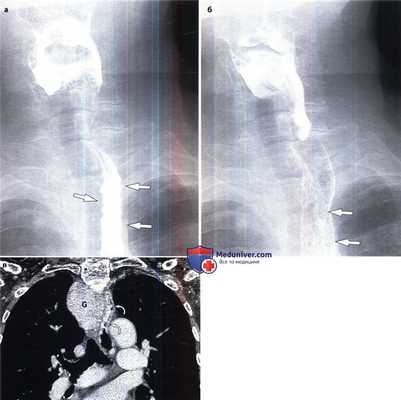

Варикозное расширение вен пищевода с нисходящим кровотоком у женщины 76 лет.

(а, б) Обратите внимание на смещение влево проксимального отдела пищевода и утолщенные бугристые складки (стрелки).

(в) При КТ с контрастированием в коронарной проекции выявлен крупный внутригрудной зоб (G), который вызывает смещение прилегающих органов.

Варикозно-расширенные вены пищевода локализуются в его проксимальном отделе (изогнутые стрелки) и представлены в виде извитых структур с гомогенным накоплением контраста.